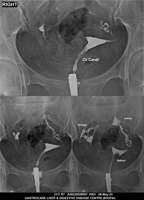

Section: HSG

Total: 49 Cases

All Categories BaM Enteroclysis Loopogram BaE Fistulogram Urethrogram HSG